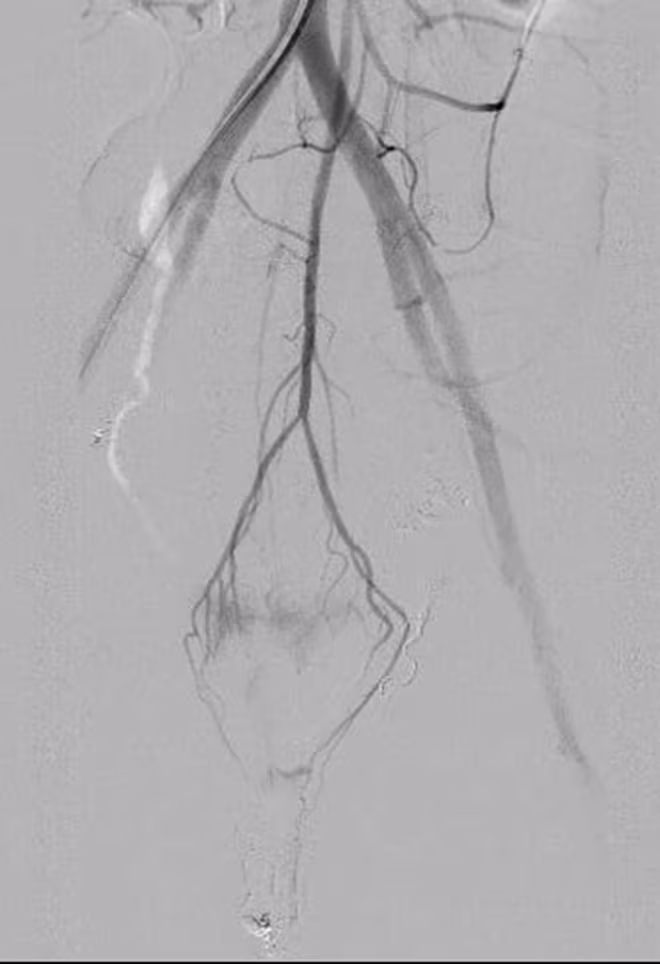

| Sau nút mạch động mạch mạc treo tràng dưới |

Bác sĩ Chuyên khoa II Phan Hoàng Giang, người trực tiếp thực hiện ca can thiệp cho phụ sản 33 tuổi này cho biết: “Đây là lần đầu tiên, chúng tôi gặp trường hợp chảy máu sau đẻ mà nguồn gốc lại từ động mạch mạc treo tràng dưới. Ca lâm sàng này rất hiếm gặp trên thế giới. Ca được báo cáo lần đầu tiên là vào năm 2015. Và trong một nghiên cứu lên đến 783 bệnh nhân thì chỉ có 8 bệnh nhân mắc (chiếm 1% các trường hợp chảy máu sau đẻ). Với những bệnh nhân đã cắt tử cung càng khó khăn trong quá trình tìm động mạch tử cung nhằm cầm máu và gây tắc. Ca sản phụ này khá phức tạp và mất nhiều thời gian hơn so với ca chảy máu sau đẻ thông thường.

“Bình thường, chúng tôi chỉ gây tắc nhánh mạch tổn thương và cầm máu tạm thời động mạch chậu trong hai bên. Tuy nhiên với bệnh nhân này, chúng tôi cần tìm thêm các nhánh chảy máu quanh trực tràng, gồm 6 nhánh mạch 2 bên: động mạch trực tràng trên, động mạch trực tràng giữa và động mạch trực tràng dưới”, BS CKII Phan Hoàng Giang cho biết thêm.

Nhớ lại khoảnh khắc “đấu trí” với tử thần, PGS.TS. Vũ Đăng Lưu, Giám đốc Trung tâm Điện Quang (Bệnh viện Bạch Mai) chia sẻ: “Sau khi xác định được nhánh chảy máu, chúng tôi phải lựa chọn vật liệu gây tắc mạch cũng như vị trí can thiệp để không bị hoại tử trực tràng. Sau 36 tiếng theo dõi an toàn, sản phụ đã được xuất viện, trở về nhà cùng chồng và 3 con thơ”.